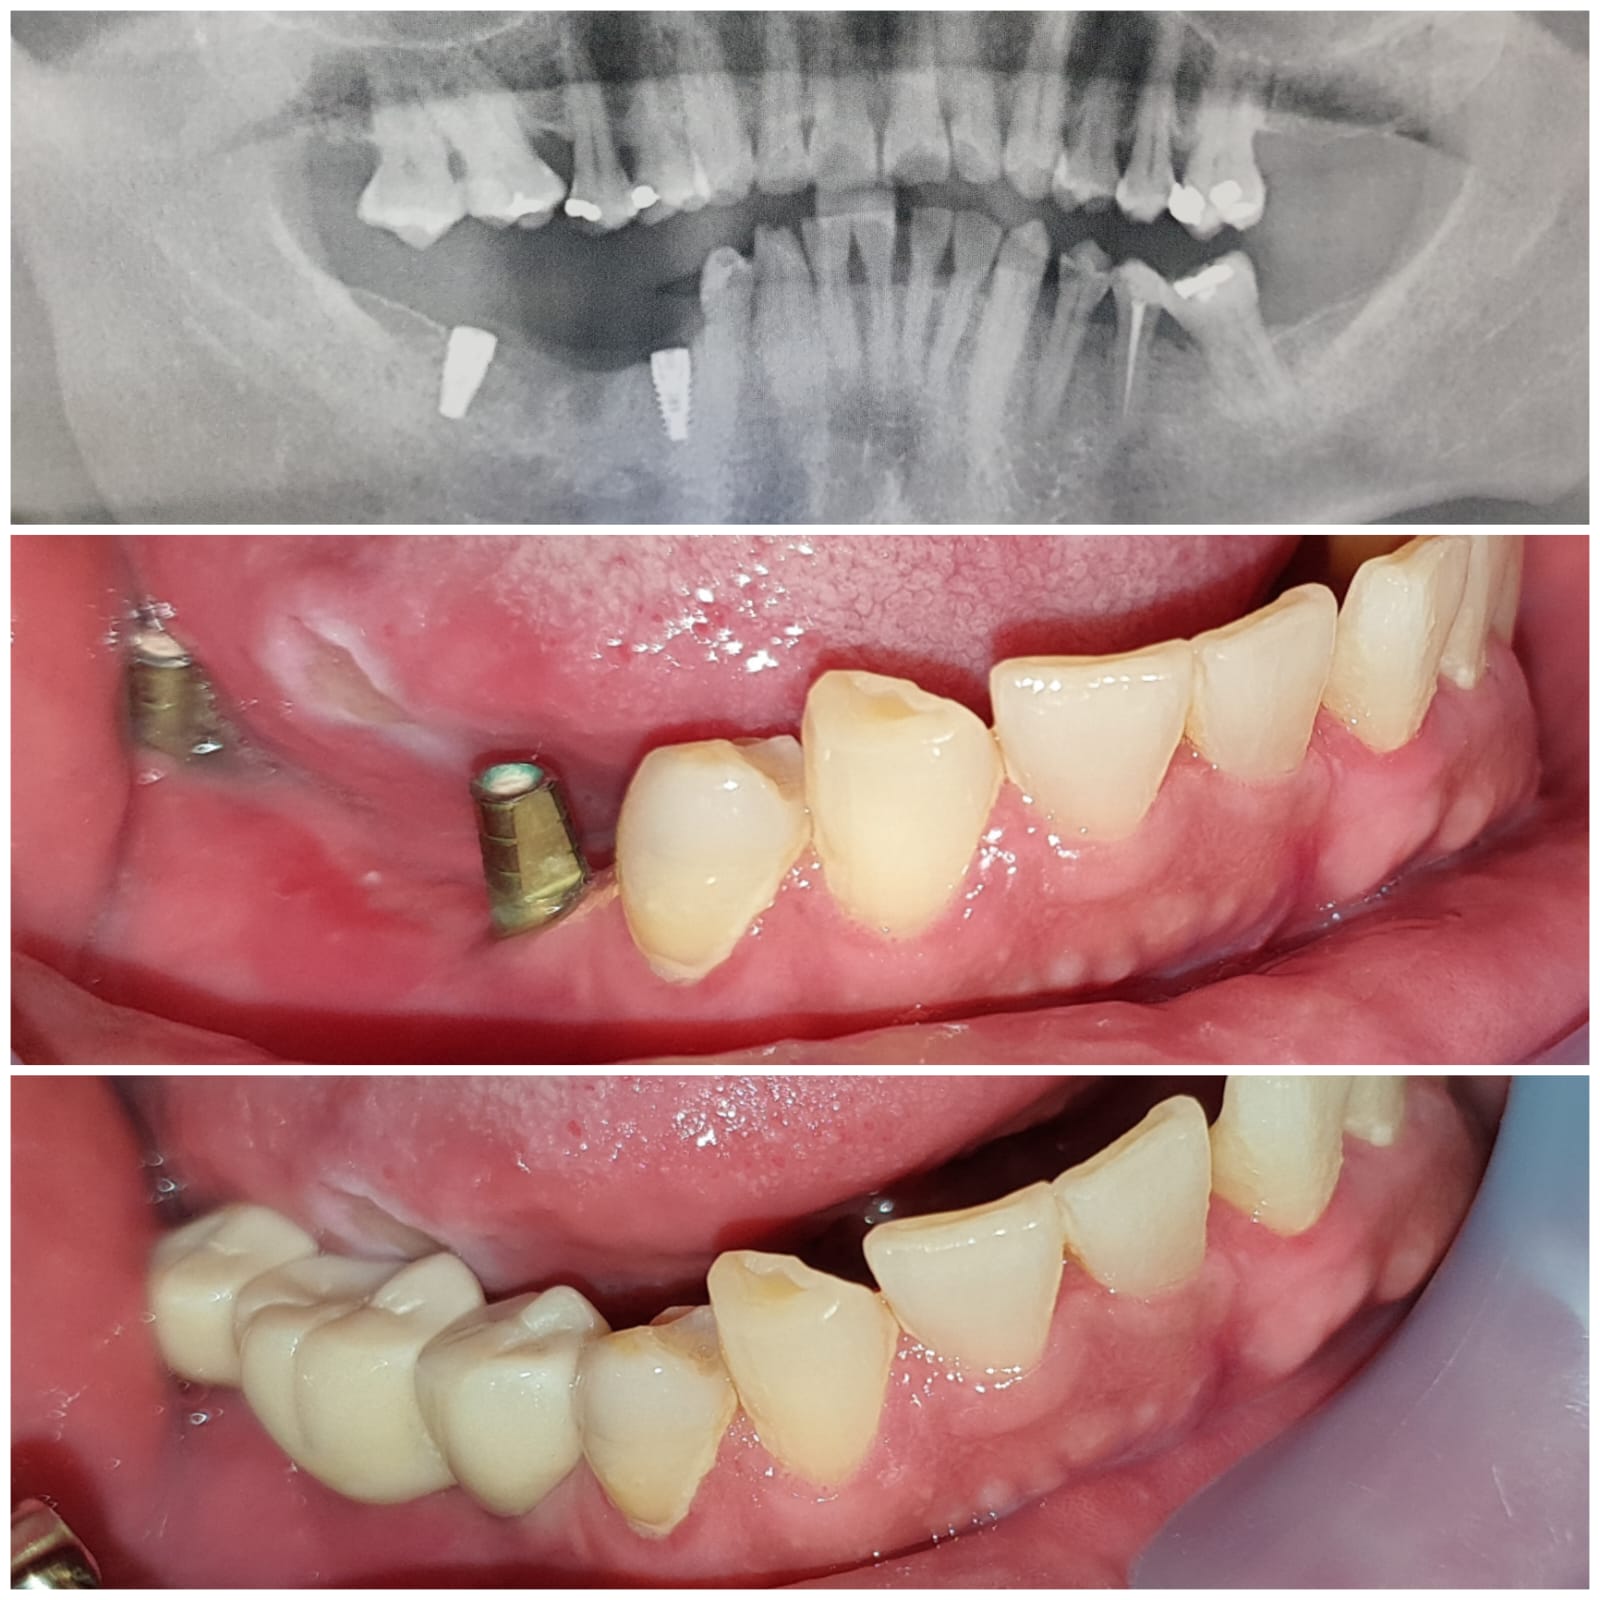

Oral Surgery & Dental Implans

Implan gigi merupakan akar gigi buatan berbentuk seperti baut yang ditanam pada rahang pasien untuk mengganti akar gigi yang hilang. Cara ini digunakan sebagai pengganti akar yang akan menahan gigi buatan untuk mengganti gigi asli yang sudah tanggal atau ompong.